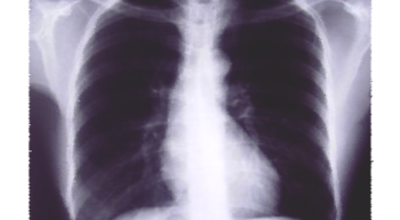

일반인이 근육통과 금이 간 경우의 차이는 거의 판별하기 힘들어요. 갈비뼈라고 하는 부분이 눈에 보이도록 붓는 것도 아니고, 멍이 들어서 아픈것도 아니기 때문이지요. 가장 정확하게 판별하는 방법은 엑스레이를 찍는 방법이지요.